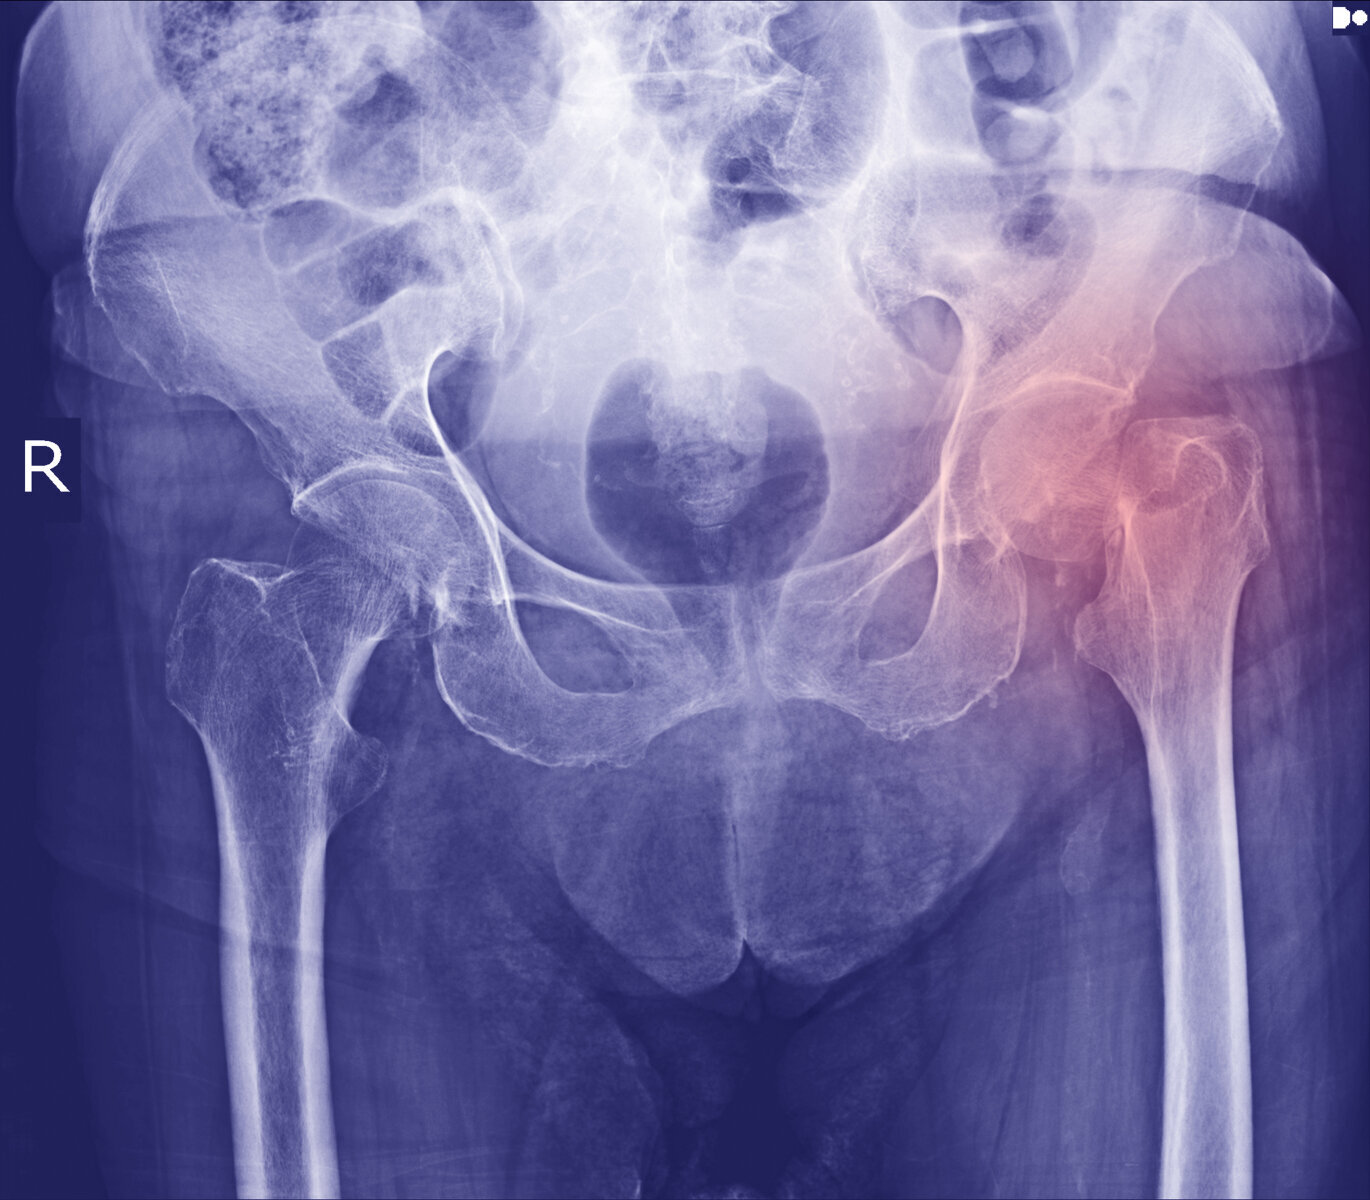

Det er høy risiko for å dø etter et hoftebrudd. Nå viser anslag fra St. Olavs hospital og NTNU at risikoen for pasienter over 70 år øker hvis de skrives ut på grunn av plassmangel.

Hvert år er det rundt 10 000 hoftebrudd i Norge. Denne gruppen pasienter er sårbar, fordi gjennomsnittsalderen er høy, og mange har flere sykdommer.

Studien omfatter 60 000 pasienter over 70 år som ble operert for hoftebrudd mellom 2008 og 2016.